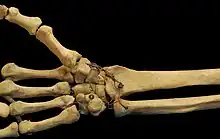

The carpometacarpal (CMC) joints are five joints in the wrist that articulate the distal row of carpal bones and the proximal bases of the five metacarpal bones.

Fingers

- The second metacarpal articulates primarily with the trapezoid and secondarily with the trapezium and capitate.

- The third metacarpal articulates primarily with the capitate,

- The fourth metacarpal articulates with the capitate and hamate.

- The fifth metacarpal articulates with the hamate.

Ligaments

These four CMC joints are supported by strong transverse and weaker longitudinal ligaments: the dorsal carpometacarpal ligaments and the volar or palmar carpometacarpal ligaments.[7]

The interosseous ligaments consist of short, thick fibers, and are limited to one part of the carpometacarpal articulation; they connect the contiguous inferior angles of the capitate and hamate with the adjacent surfaces of the third and fourth metacarpal bones.